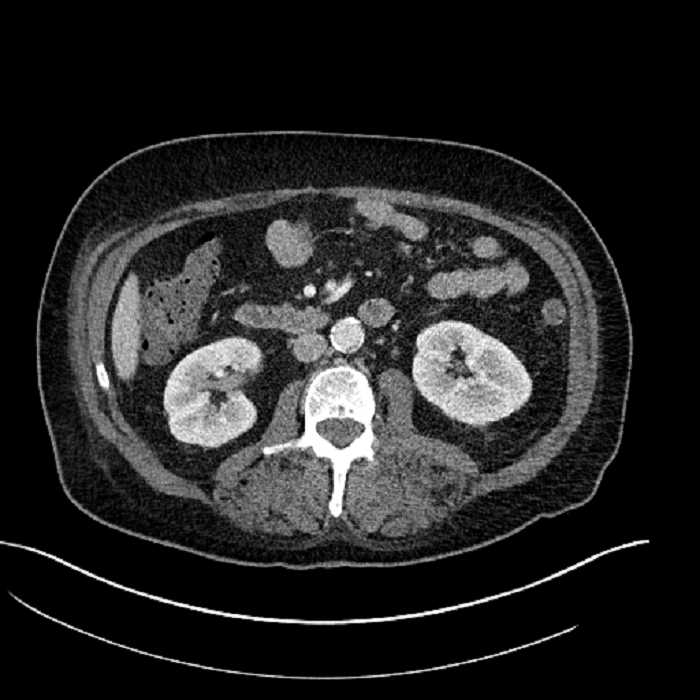

• Large fluid density structure in hepatic segments 7 and 8 measuring 10 x 7 x 7 cm with internal septation and circumferential ill-defined low density compatible with edema

• Peripherally enhancing subcapsular collections along the anterior margin of the left hepatic lobe measuring 3 x 1 cm and 2 x 1 cm

• Clearly marginated fluid density structure in segment 7 and several other scattered tiny hypodensities, which likely represent cysts

• Hepatic abscess

Acute sigmoid diverticulitis complicated by a small contained perforation and a large abscess in the right hepatic lobe. Additional small subcapsular abscesses along the anterior margin of the left hepatic lobe.

• The classic CT imaging appearance is a double target sign with internal low density surrounded by an internal enhancing rim (capsule) and a low density external rim (edema)

Hepatic abscess showing the double target sign with low density internally surrounded by a thin inner enhancing rim (red arrow) and ill-defined outer low density rim (yellow arrow). Blue arrow indicates an internal septation. Red arrows: additional smaller subcapsular abscesses. Red arrow: focal contained perforation associated with diverticulitis.